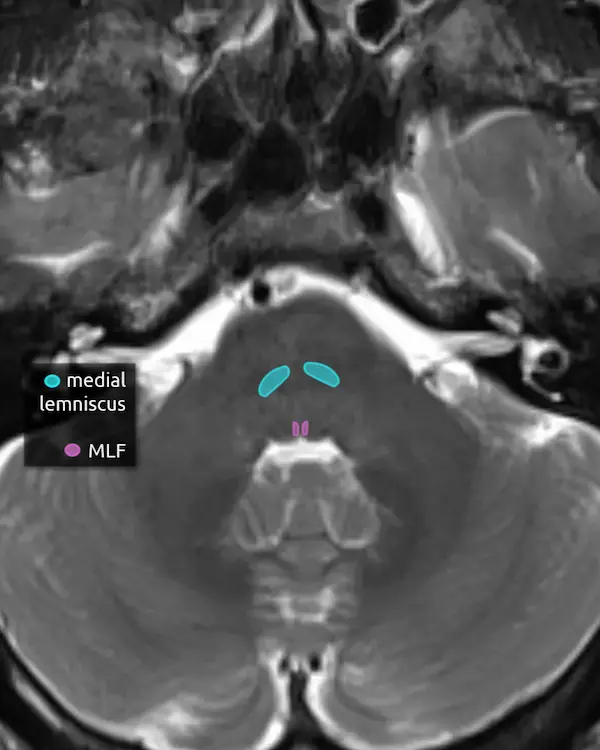

5. Medial lemniscus

The medial lemniscus is an ascending sensory pathway that spans the entire brainstem, originating at the nucleus gracilis and cuneatus (see level 5) in the medulla and ending at the primary sensory nucleus of the thalamus: the ventral posterolateral nucleus (VPL). It begins medially in the medulla and becomes more lateral at the level of the midbrain, located in close proximity to the substantia nigra. It is responsible for vibration sensation, fine touch, and proprioception.

Lesions involving the medial lemniscus may cause contralateral loss of vibration sensation and joint position sensation on physical exam with symptoms of numbness and paresthesias.

6. Medial longitudinal fasciculus (MLF)

The MLF is an ascending and descending pathway responsible for coordinating eye movements. It connects all of the cranial nerve nuclei that innervate the extraocular muscles (CN III, IV, and VI) as well as the vestibulocochlear nuclei (CN VIII). The MLF spans the entire brainstem, however lesions producing visual symptoms will probably be in the midbrain or pons.

There are characteristic syndromes that result from damage to the MLF, most commonly internuclear ophthalmoplegia (INO) or INO-plus syndromes. A common clinical scenario is a patient with multiple sclerosis who develops a demyelinating lesion along the MLF in the midbrain or pons and presents with bilateral INO.